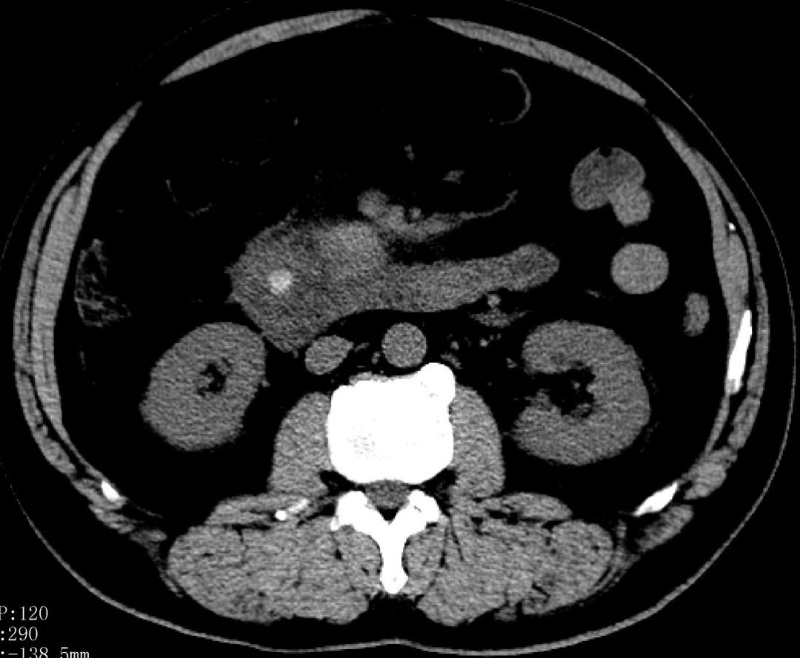

2023年10月28日,李大爺前往我院就診,經過醫生耐心詢問,得知李大爺上腹部疼痛劇烈,伴腹脹、嘔吐,既往有糖尿病病史及高血壓病病史。化驗結果顯示:血淀粉酶3755 U/L,血脂肪酶2537 U/L,尿淀粉酶10298 U/L。血總膽紅素108.8 umol/L,直接膽紅素54.19 umol/L,間接膽紅素54.61 umol/L。CT平掃檢查:膽總管下段結石(大小約12mm×9mm)伴肝內外膽管擴張,膽囊腫大,急性胰腺炎,腹腔積液,胸腔積液。

入院診斷出李大爺患有急性胰腺炎,膽總管結石伴急性化膿性梗阻性膽管炎,2型糖尿病,高血壓病。

在治療24小時后,李大爺突然病情加重,腹痛腹脹加重,腹部壓痛反跳痛加重,發熱體溫38℃,心率快達130次/分,呼吸35次/分,胸悶,血氧飽和度85%,血壓不穩定。復查血鈣降低1.89 mmol/L,血膽紅素升高,總膽紅素173.36 umol/L,直接膽紅素87.13 umol/L,間接膽紅素86.23 umol/L。李大爺表現為重癥急性胰腺炎伴膽道有梗阻及化膿性膽管炎,并有繼續惡化趨勢。

情況緊急,普通外科團隊第一時間進行術前病情討論,經過反復論證,普通外科團隊立即給予在插管全麻下行經皮經肝膽管穿刺置管引流術(PTCD)。